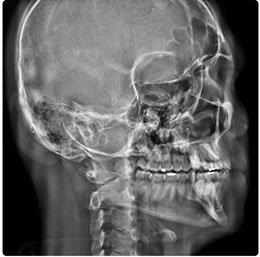

Eagle 2D Pan/Tele

El Eagle 2D Pan/Tele ofrece todos los exámenes en el perfil panorámico (panorámica estándar, senos maxilares, baja dosis, bitewing, ATM, ortogonalidad perfeccionada, panorámica infantil y bitewing ortogonalidad perfeccionada) y todos los exámenes en el perfil cefalométrico (Posteroanterior, Antero-posterior, 45 Grados, Lateral, Carpal, PA de Walters, Axial Bazal, Hirtz).

Telerradiografía Lateral

Telerradiografía Antero Posterior